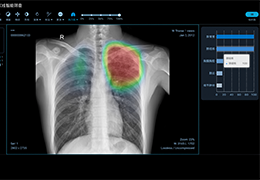

ART-Plan™ Artificial Intelligence Contouring